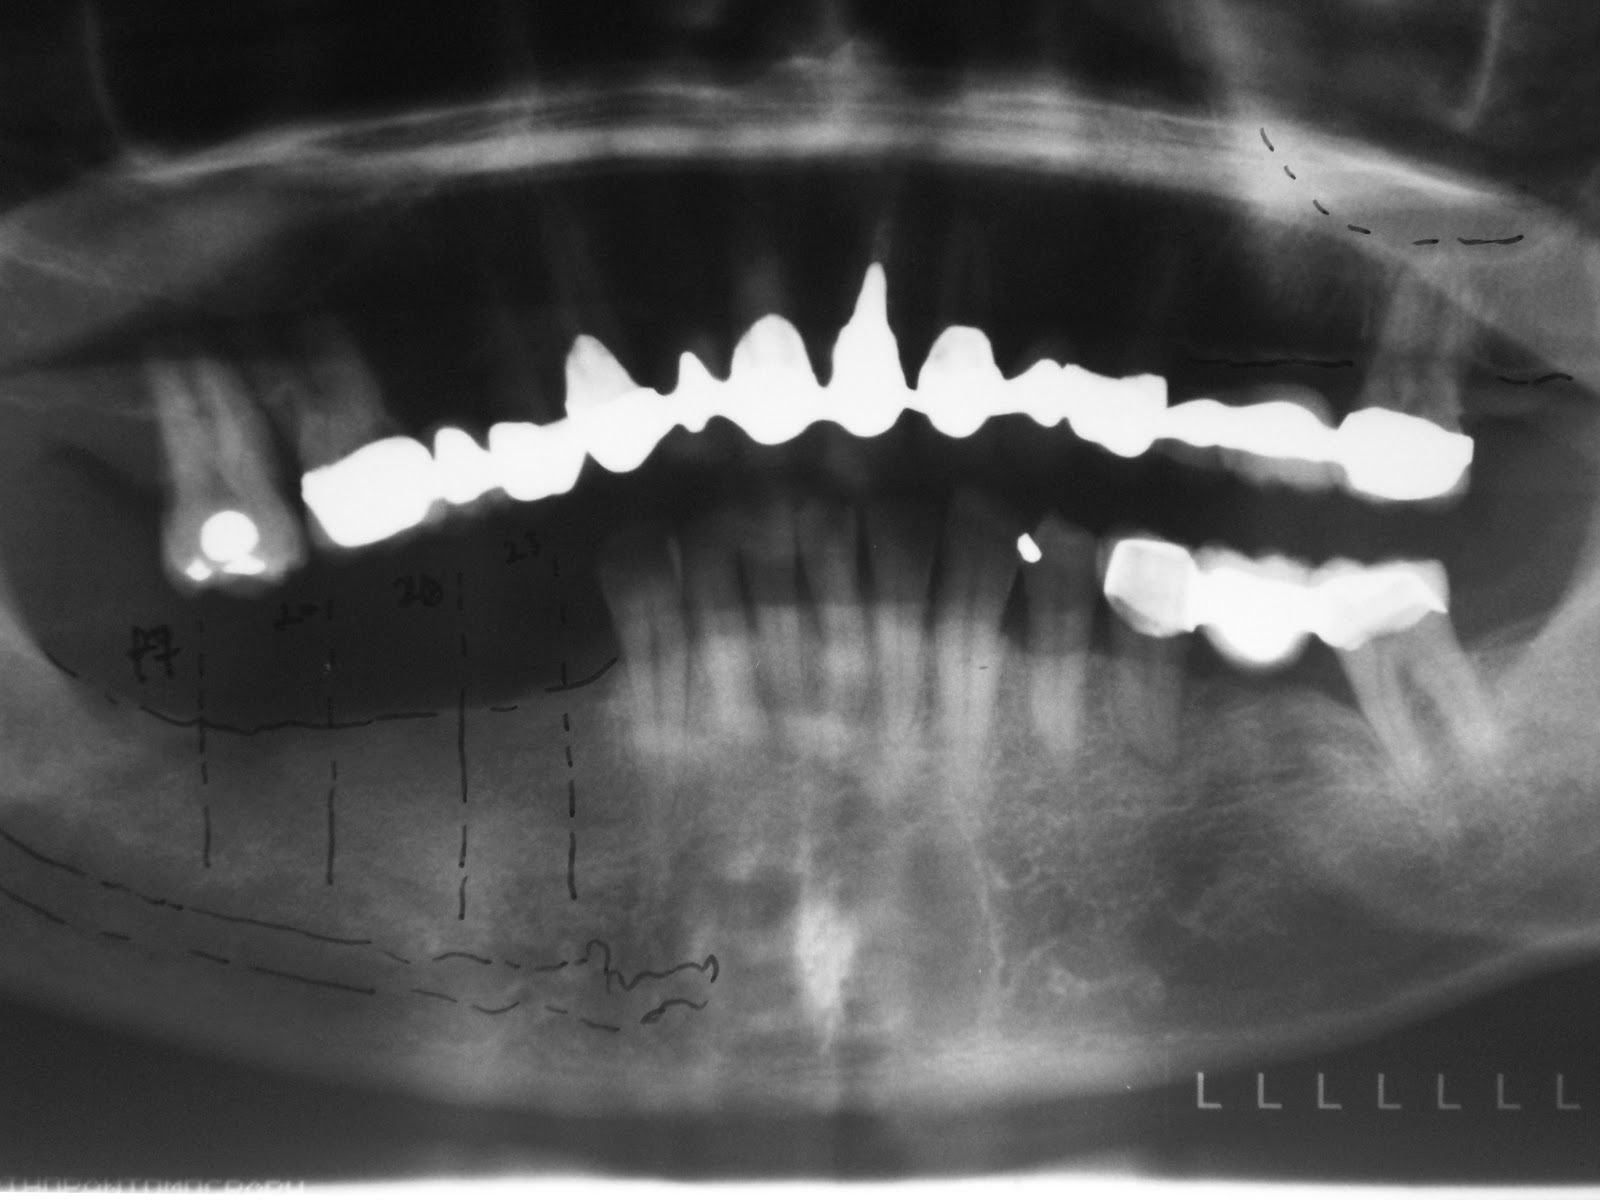

Dental Implantology A KNIFE EDGED RIDGE CASE Knife Edge Dental Feather edge, knife edge, chisel edge, but researchers. the shoulderless type of tooth crown preparation (also known as bevel preparation) has been referred to differently according to the rising taper: forthcoming will be the first in a series of articles detailing (1) idealizing a knife edge ridge, placing sdis, and relining/retaining an existing denture; (2) idealizing a knife. Knife Edge Dental.

Dental Implantology A KNIFE EDGED RIDGE CASE Knife Edge Dental forthcoming will be the first in a series of articles detailing (1) idealizing a knife edge ridge, placing sdis, and relining/retaining an existing denture; the shoulderless type of tooth crown preparation (also known as bevel preparation) has been referred to differently according to the rising taper: (2) idealizing a knife edge ridge, placing sdis,. a sharp bony. Knife Edge Dental.

Dental Implantology A KNIFE EDGED RIDGE CASE Knife Edge Dental (2) idealizing a knife edge ridge, placing sdis,. the shoulderless type of tooth crown preparation (also known as bevel preparation) has been referred to differently according to the rising taper: a sharp bony ridge is a frequent problem among the edentulous patients and commonly occur in the mandible in the edentulous patient [ 10 ]. forthcoming will. Knife Edge Dental.

Dental Implantology A KNIFE EDGED RIDGE CASE Knife Edge Dental a sharp bony ridge is a frequent problem among the edentulous patients and commonly occur in the mandible in the edentulous patient [ 10 ]. the shoulderless type of tooth crown preparation (also known as bevel preparation) has been referred to differently according to the rising taper: (2) idealizing a knife edge ridge, placing sdis,. Feather edge, knife. Knife Edge Dental.

Dental Implantology A KNIFE EDGED RIDGE CASE Knife Edge Dental a sharp bony ridge is a frequent problem among the edentulous patients and commonly occur in the mandible in the edentulous patient [ 10 ]. (2) idealizing a knife edge ridge, placing sdis,. forthcoming will be the first in a series of articles detailing (1) idealizing a knife edge ridge, placing sdis, and relining/retaining an existing denture; Feather. Knife Edge Dental.